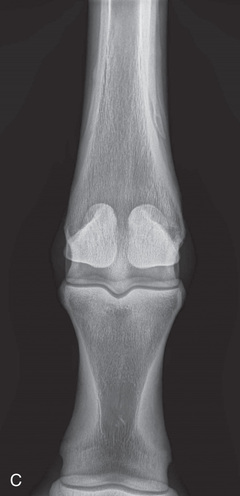

| Metacarpophalangeal/metatarsophalangeal joint/proximal sesamoid bones (fetlock) | Dorsal 10-degree proximal–palmarodistal oblique (D10Pr-PaDiO) | Dorsopalmar (DP) |

| Stifle | Lateromedial (LM) | Lateral (L) |

| Caudoproximal-craniodistal (CdPr-CrDi) | Caudocranial (CdCr) | |

Radiography of the femorotibial joint (stifle) is difficult because of the thickness of the surrounding tissue and the sensitive nature of this region. Because of the depth of the muscle in the femoral region, the caudocranial projection demonstrates little above the joint space. Radiographs of this region should be attempted only if the patient is cooperative. Safety is paramount in radiography of the hind region of the horse. Sedation or a twitch may be used; general anesthesia is also to be considered.

| Stifle | Caudocranial CdCr (Standard) | Caudoproximal-craniodistal standing (CdPr-CrDi) | Weight-bearing with limbs evenly on ground and vertical cassette against cranial aspect of patella at right angle to body wall, placed as far proximal and pushed as far medially as abdomen permits. | Caudal to the joint and directed downward to obtain a “tunnel” view of the distal femur. |

| Lateral (Standard) | Lateromedial | Weight-bearing with limbs evenly on ground and cassette against medial aspect of joint. | Laterally, parallel to the ground and centered distal and caudal to the patella. | |